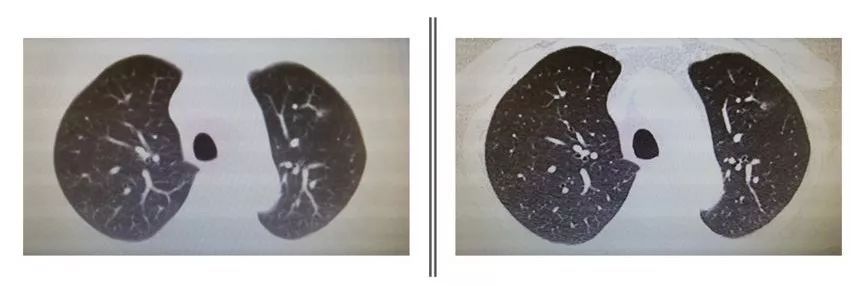

薄层CT,顾名思义就是层距比较小的CT,一般层距达到5mm就可称为薄层CT,为达到更小的层距,需要使用更先进的高分辨率CT(HRCT)。更小的层距、更高分辨率的算法以及更大的矩阵可以带来更多的信息。目前对于肺部疾病最常用的就是高分辨率薄层CT,与常规CT相比,精度更高,分辨率更强,可以看清肺内细小结构。HRCT与常规CT图像区别请看下图。

(左图为常规CT,右图为同一病例HRCT)